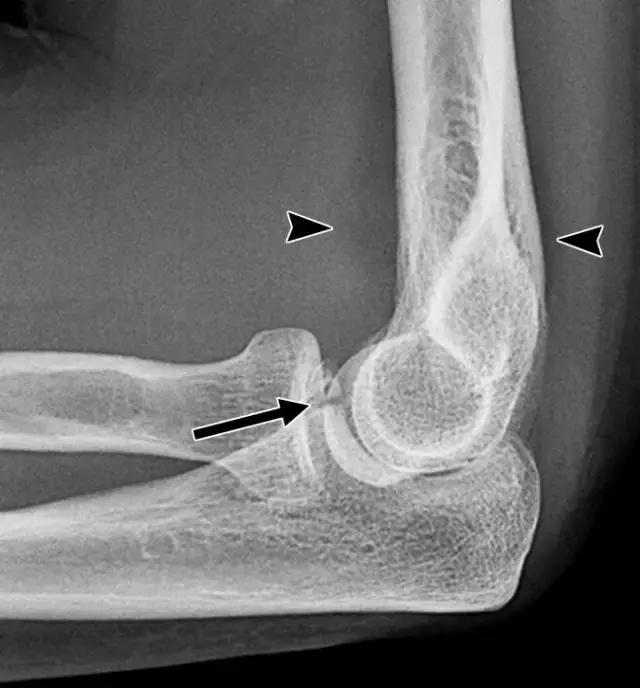

检查X线片冠状突骨折时应进一步横断面成像评估(图4A)。MRI有助于评估与肘关节脱位相关的软组织和骨髓损伤[17,26](图4B)。

图4A -45岁女性,肘关节脱位。侧位片显示关节积液(箭头)和冠状突尖端横向骨折(箭头)。